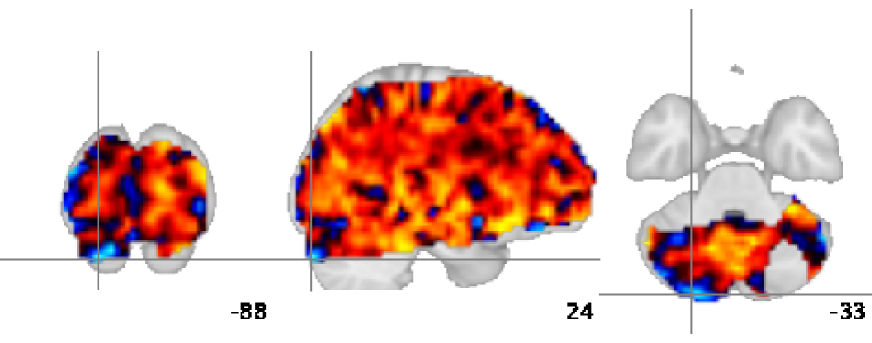

4 fMRI study

We apply our method to fMRI data for 12 subjects at rest from a previous study [8]. 820 volumes were acquired with a repetition time (TR) of s. We run the procedure (ICA analysis and thresholding) for single-subject data on the first 40 principal components. For fMRI data, the ground truth is not known, so we generate degraded datasets from the original dataset, and consider the latter as a pseudo ground truth to quantify error rates. This procedure quantifies consistency of the estimator in the presence of noise. To generate degraded datasets while retaining observations of the same brain activity, we use one volume out of 3. The effective TR of the down-sampled datasets is s. This sampling rate is enough to retain most of the hemodynamic response, convolved by the 6-second-long response function. In addition, the 3 resulting interleaved time series sample different high-frequency noise that confounds the signal of interest. Thresholded ICs estimated on the various resampled datasets for one subject are matched with the corresponding pseudo ground truth. Fig.Β 3 presents pseudo ground truth and downsampled data. On non-thresholded ICs, we can see that the level of background noise is indeed higher in ICs learned on downsampled data. We run the MELODIC mixing model on the ICs to compare sensitivity (false negatives) and specificity (false positives).

ICs estimated on fMRI data most often display a few salient features related to anatomical regions and may be interpreted as brain networks. On such IC, both our thresholding procedure and MELODICβs mixture model extract similar regions, although our procedure yields fewer small clusters outside of the main segmented areas (see Fig.Β 3, top). In contrast, some ICs, representative of non-cognitive processes such as blood flow or movement, are very fragmented and diffuse with no region strongly standing out. On these ICs, a mixture model fits the null distribution to the center of the histogram, and thus selects large regions, whereas our thresholding procedure selects very few voxels, as it does not consider the component by itself, but as part of the complete multivariate signal (see Fig.Β 3, bottom).